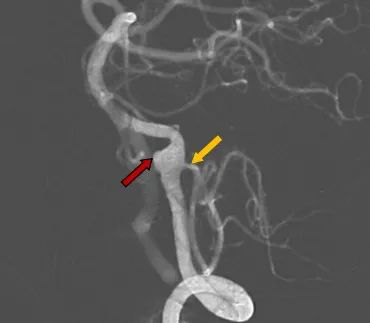

图3:脑血管造影(DSA)显示右侧椎动脉动脉瘤,

小脑后下动脉从动脉瘤处发出